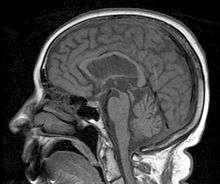

This patient presented with progressive dementia, ataxia and incontinence. A clinical diagnosis of normal pressure hydrocephalus was entertained. Imaging did not support this, however, and on formal testing abnormal nystagmus and eye movements were detected. A sagittal view of the CT/MRI scan shows atrophy of the midbrain, with preservation of the volume of the pons. This appearance has been called the "Hummingbird sign" or "Penguin sign". There is also atrophy of the tectum, particularly the superior colliculi. These findings suggest the diagnosis of progressive supranuclear palsy.[4]